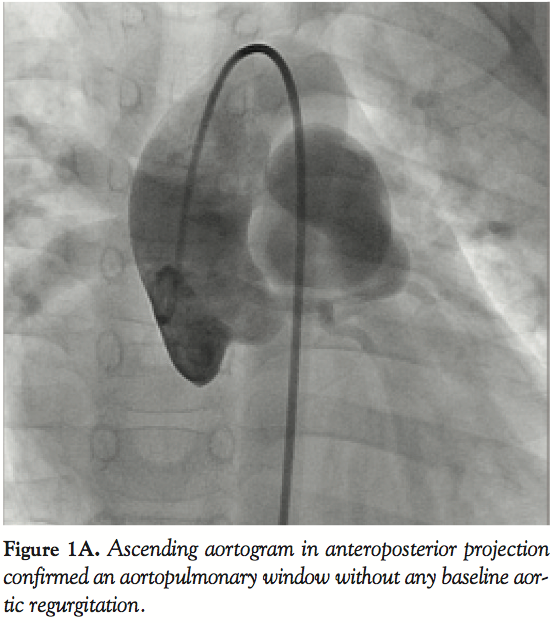

image